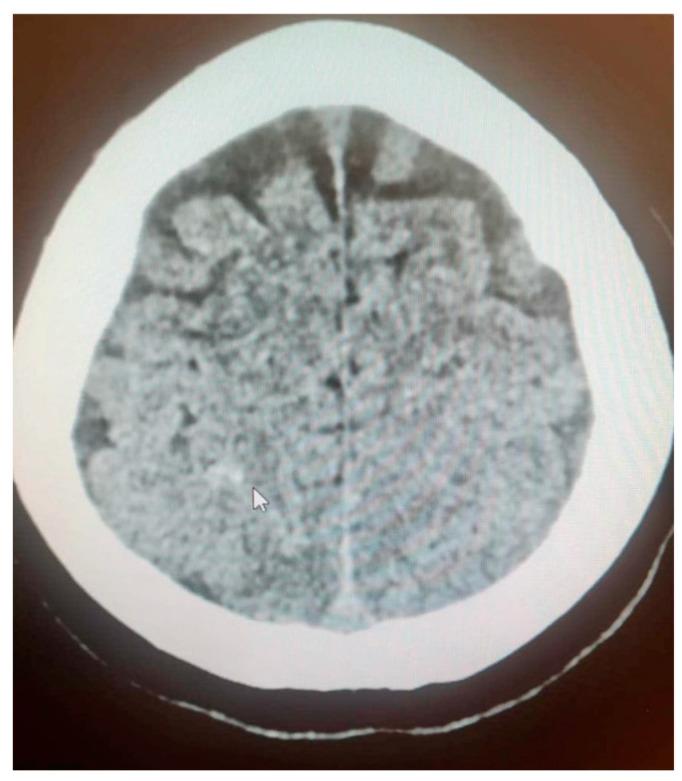

Intracranial hemorrhage is a rare yet potentially devastating event during pregnancy with a significant risk of maternal and fetal mortality and morbidity. The risk of intracranial hemorrhage increases during the third trimester of pregnancy and is greatest during labor and the postpartum period. Interdisciplinary diagnosis and treatment of the pregnant population often begins in the emergency department setting and is key to increasing patient survival rates through immediate and adequate treatment, including emergency medicine, neurosurgical and obstetrical procedures. A unique case report with a diagnostic pathway for intracranial hemorrhage due to eclampsia in a primipara at 24 weeks of gestation is presented, illustrating potential diagnostic dilemmas as the patient rapidly progresses into hemolysis, elevated liver enzymes and low platelets syndrome. A literature review was conducted to uncover the etiology of intracranial hemorrhage during pregnancy, as well as its diagnostic challenges and treatment. Pregnancy should not be viewed as a barrier to performing angiography or endovascular treatment for vascular causes of intracranial hemorrhage. Patient transport to a tertiary reference center and the interdisciplinary cooperation of specialists are key to achieving correct and rapid treatment. Continuous prevention of preeclampsia and patient education are necessary to decrease the incidence of eclampsia and its complications. Key message: Intracranial hemorrhage and eclampsia in pregnant patients are rare yet may result in high rates of maternal and fetal morbidity and mortality. The diagnostic process is difficult and requires interdisciplinary cooperation to start the correct treatment immediately.

颅内出血是孕期罕见但可能具有毁灭性的事件,母婴死亡和发病风险显著。颅内出血风险在妊娠晚期增加,在分娩期和产后期间最高。对孕妇群体的多学科诊断和治疗通常在急诊科开始,通过包括急诊医学、神经外科和产科手术在内的及时且充分的治疗来提高患者存活率是关键。本文呈现了一例独特病例报告,涉及一名妊娠24周初产妇因子痫导致颅内出血的诊断路径,该病例展示了随着患者迅速发展为溶血、肝酶升高和血小板减少综合征时可能出现的诊断困境。进行了文献综述以揭示孕期颅内出血的病因及其诊断挑战和治疗方法。不应将妊娠视为对因颅内出血的血管病因进行血管造影或血管内治疗的障碍。将患者转运至三级转诊中心以及专家的多学科合作是实现正确快速治疗的关键。持续预防子痫前期和对患者进行教育对于降低子痫及其并发症的发生率是必要的。关键信息:孕妇颅内出血和子痫罕见,但可能导致母婴高发病率和死亡率。诊断过程困难,需要多学科合作以立即开始正确治疗。